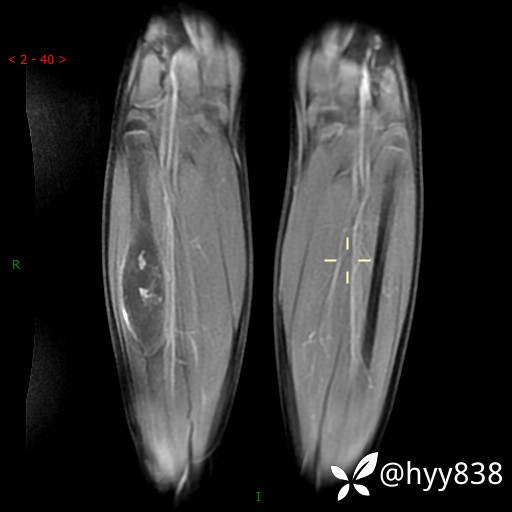

MRI 增强(cor+sag+axi)